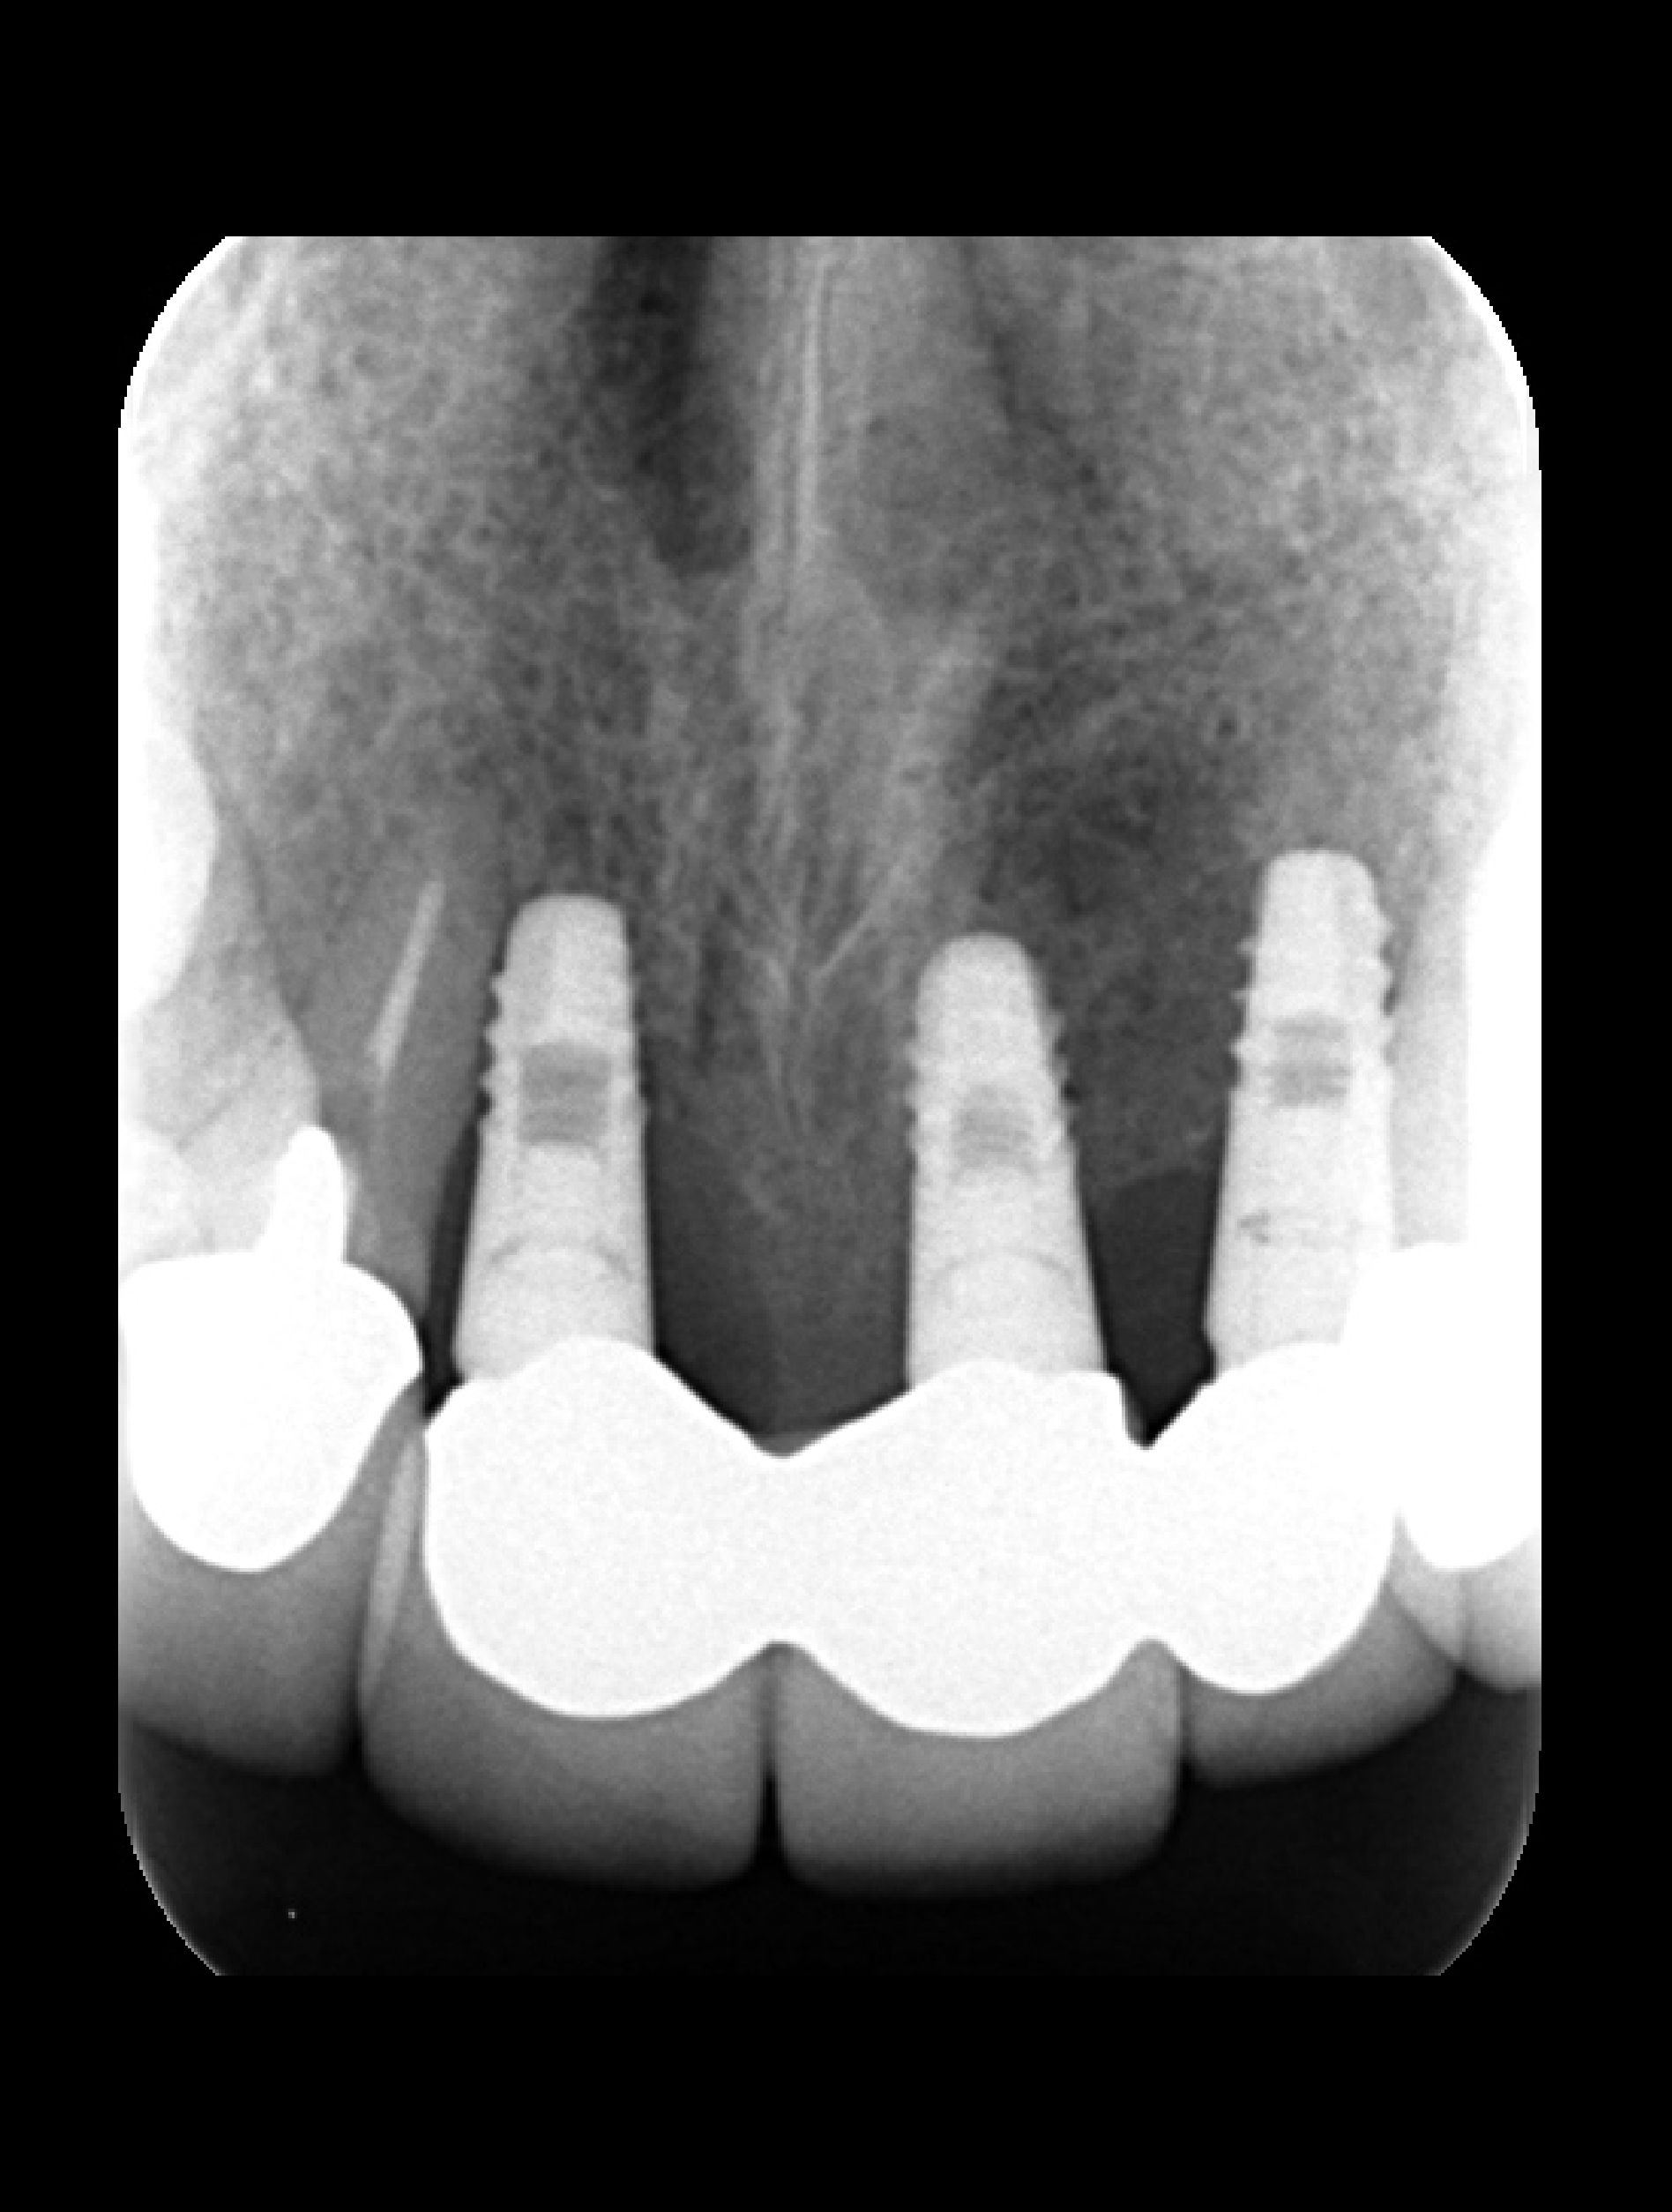

失敗例3 骨が圧倒的に足りていない

これは仮歯を使って、歯の位置をシミュレーションしたときの写真です。圧倒的に骨が足りないことがおわかりいただけると思います。次にもう1枚写真をお見せします。

これが当院に来院した時の状態です。骨が足りないため歯が長くなるだけではなく、高さも不均一です。また、歯茎の形が不自然で審美的に不十分であることがわかります。これらはインプラント・歯周病・審美歯科の技術が高いレベルで揃っていなければ解決できません。